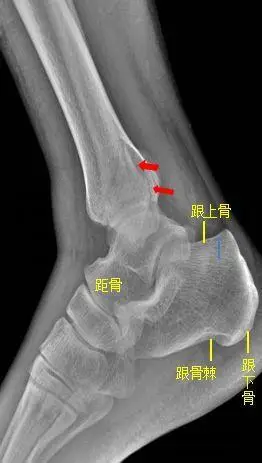

足部骨折x线照片,斜位图.

临床申请单摄足正斜位片

所示右侧腓骨远端见斜行骨折线,骨折端对位对线尚可.右腓骨远端骨折.